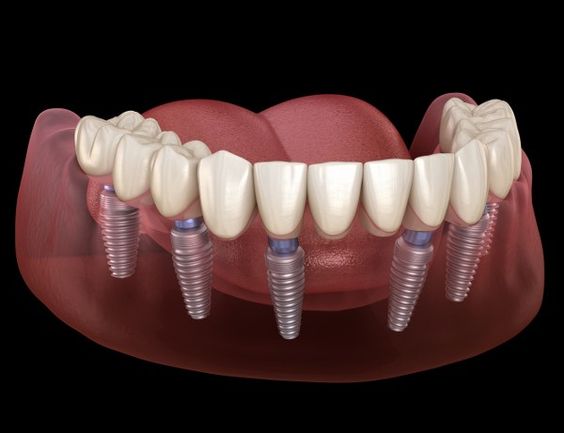

Технология «All-on-4» и «All-on-6».

Если вы потеряли все свои зубы, мы можем предложить имплантаты для фиксации постоянного функционального и эстетичного протеза. Количество имплантатов, необходимых для поддержки полного арочного моста, будет зависеть от анатомии кости челюсти, количества требуемых зубов, типа требуемого моста и зубов-антагонистов.

«All-on-4» — тщательно спланированная процедура, позволяющая разместить всего 4 или 6 имплантатов единовременно для их немедленной нагрузки с полным арочным мостом или протезом, включающим 10, 12 или 14 зубов.

Два имплантата расположены во фронтальной части ротовой полости, а 2 (4) расположены под углом чуть кзади, чтобы обеспечить фиксацию, а также избежать повреждения важных структур, таких как нервы и пазухи. Это можно сделать как на верхних, так и на нижних челюстях.